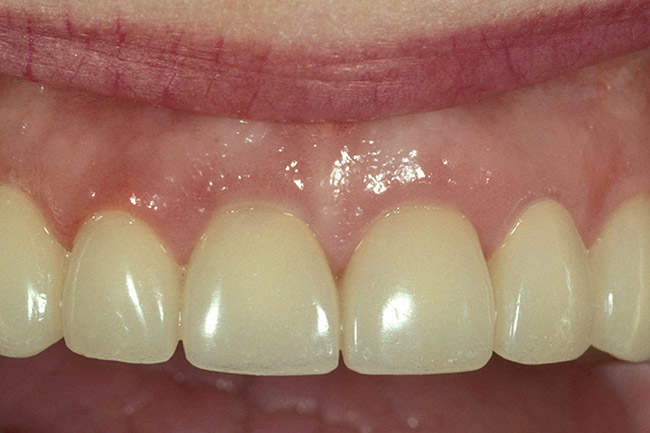

Figure 6  This 78-year-old female presented with maxillary anterior restorations placed 6 months earlier. She is unhappy with the fact that the margins are exposed and the tissue has receded following placement.

Figure 6

Figure 7   Sulcus depth from the existing attachment to the level of the existing margin is slightly greater than 3 mm. This is a patient who had an altered eruption pattern and a sulcus at the time these restorations were placed of over 3 mm.

Figure 7

Figure 8  Sounding to bone reveals a 3.5-mm distance, even following the recession.

Figure 8

Figure 9  The decision was made to perform a gingivectomy, leaving a 1-mm sulcus, then prepare the teeth 0.5 mm subgingivally on the same day.

Figure 9

Figure 10  Note that 4 to 6 weeks following the gingivectomy and re-preparation, the tissue is rebounding coronally over the margins of the temporary restorations.

Figure 10

Figure 11  This is a 4-year recall photograph following placement of the final restorations.

Figure 11